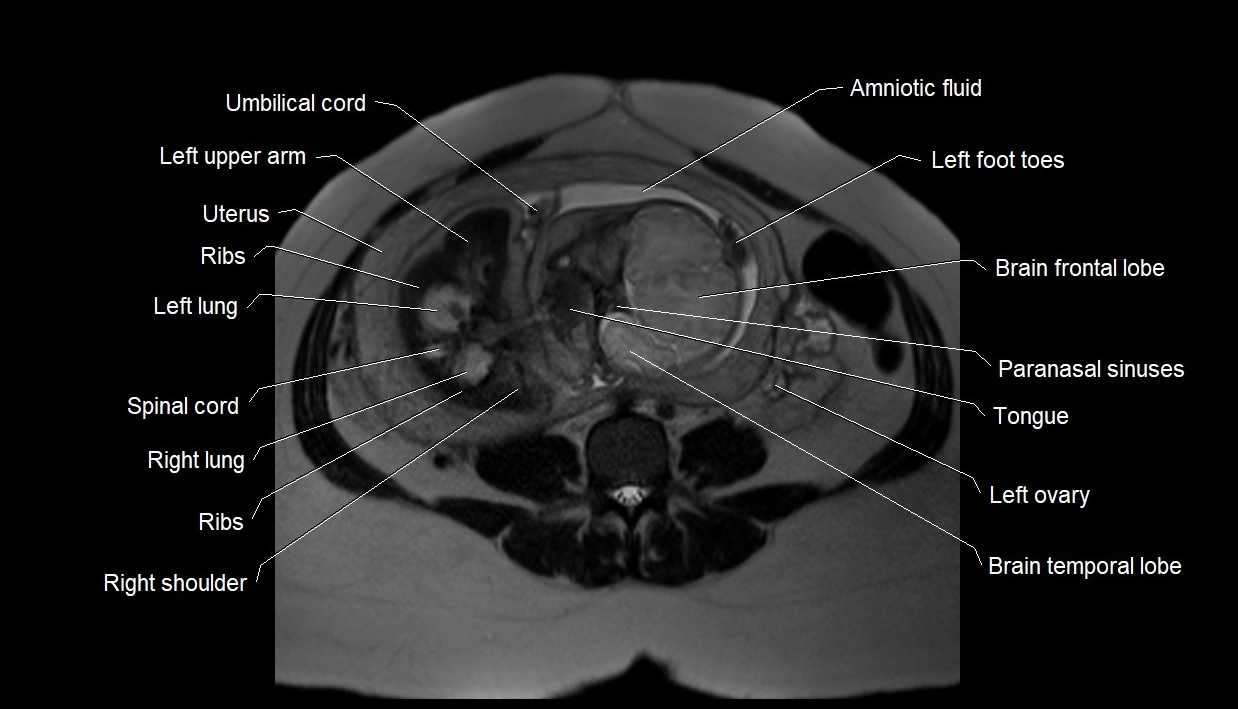

MRI Appearance

T2 HASTE (T2 GRE):

• Amniotic fluid shows very bright hyperintense signal

• Provides natural contrast against fetus and placenta

• Small particles (vernix) may appear as scattered hypointense foci within bright fluid